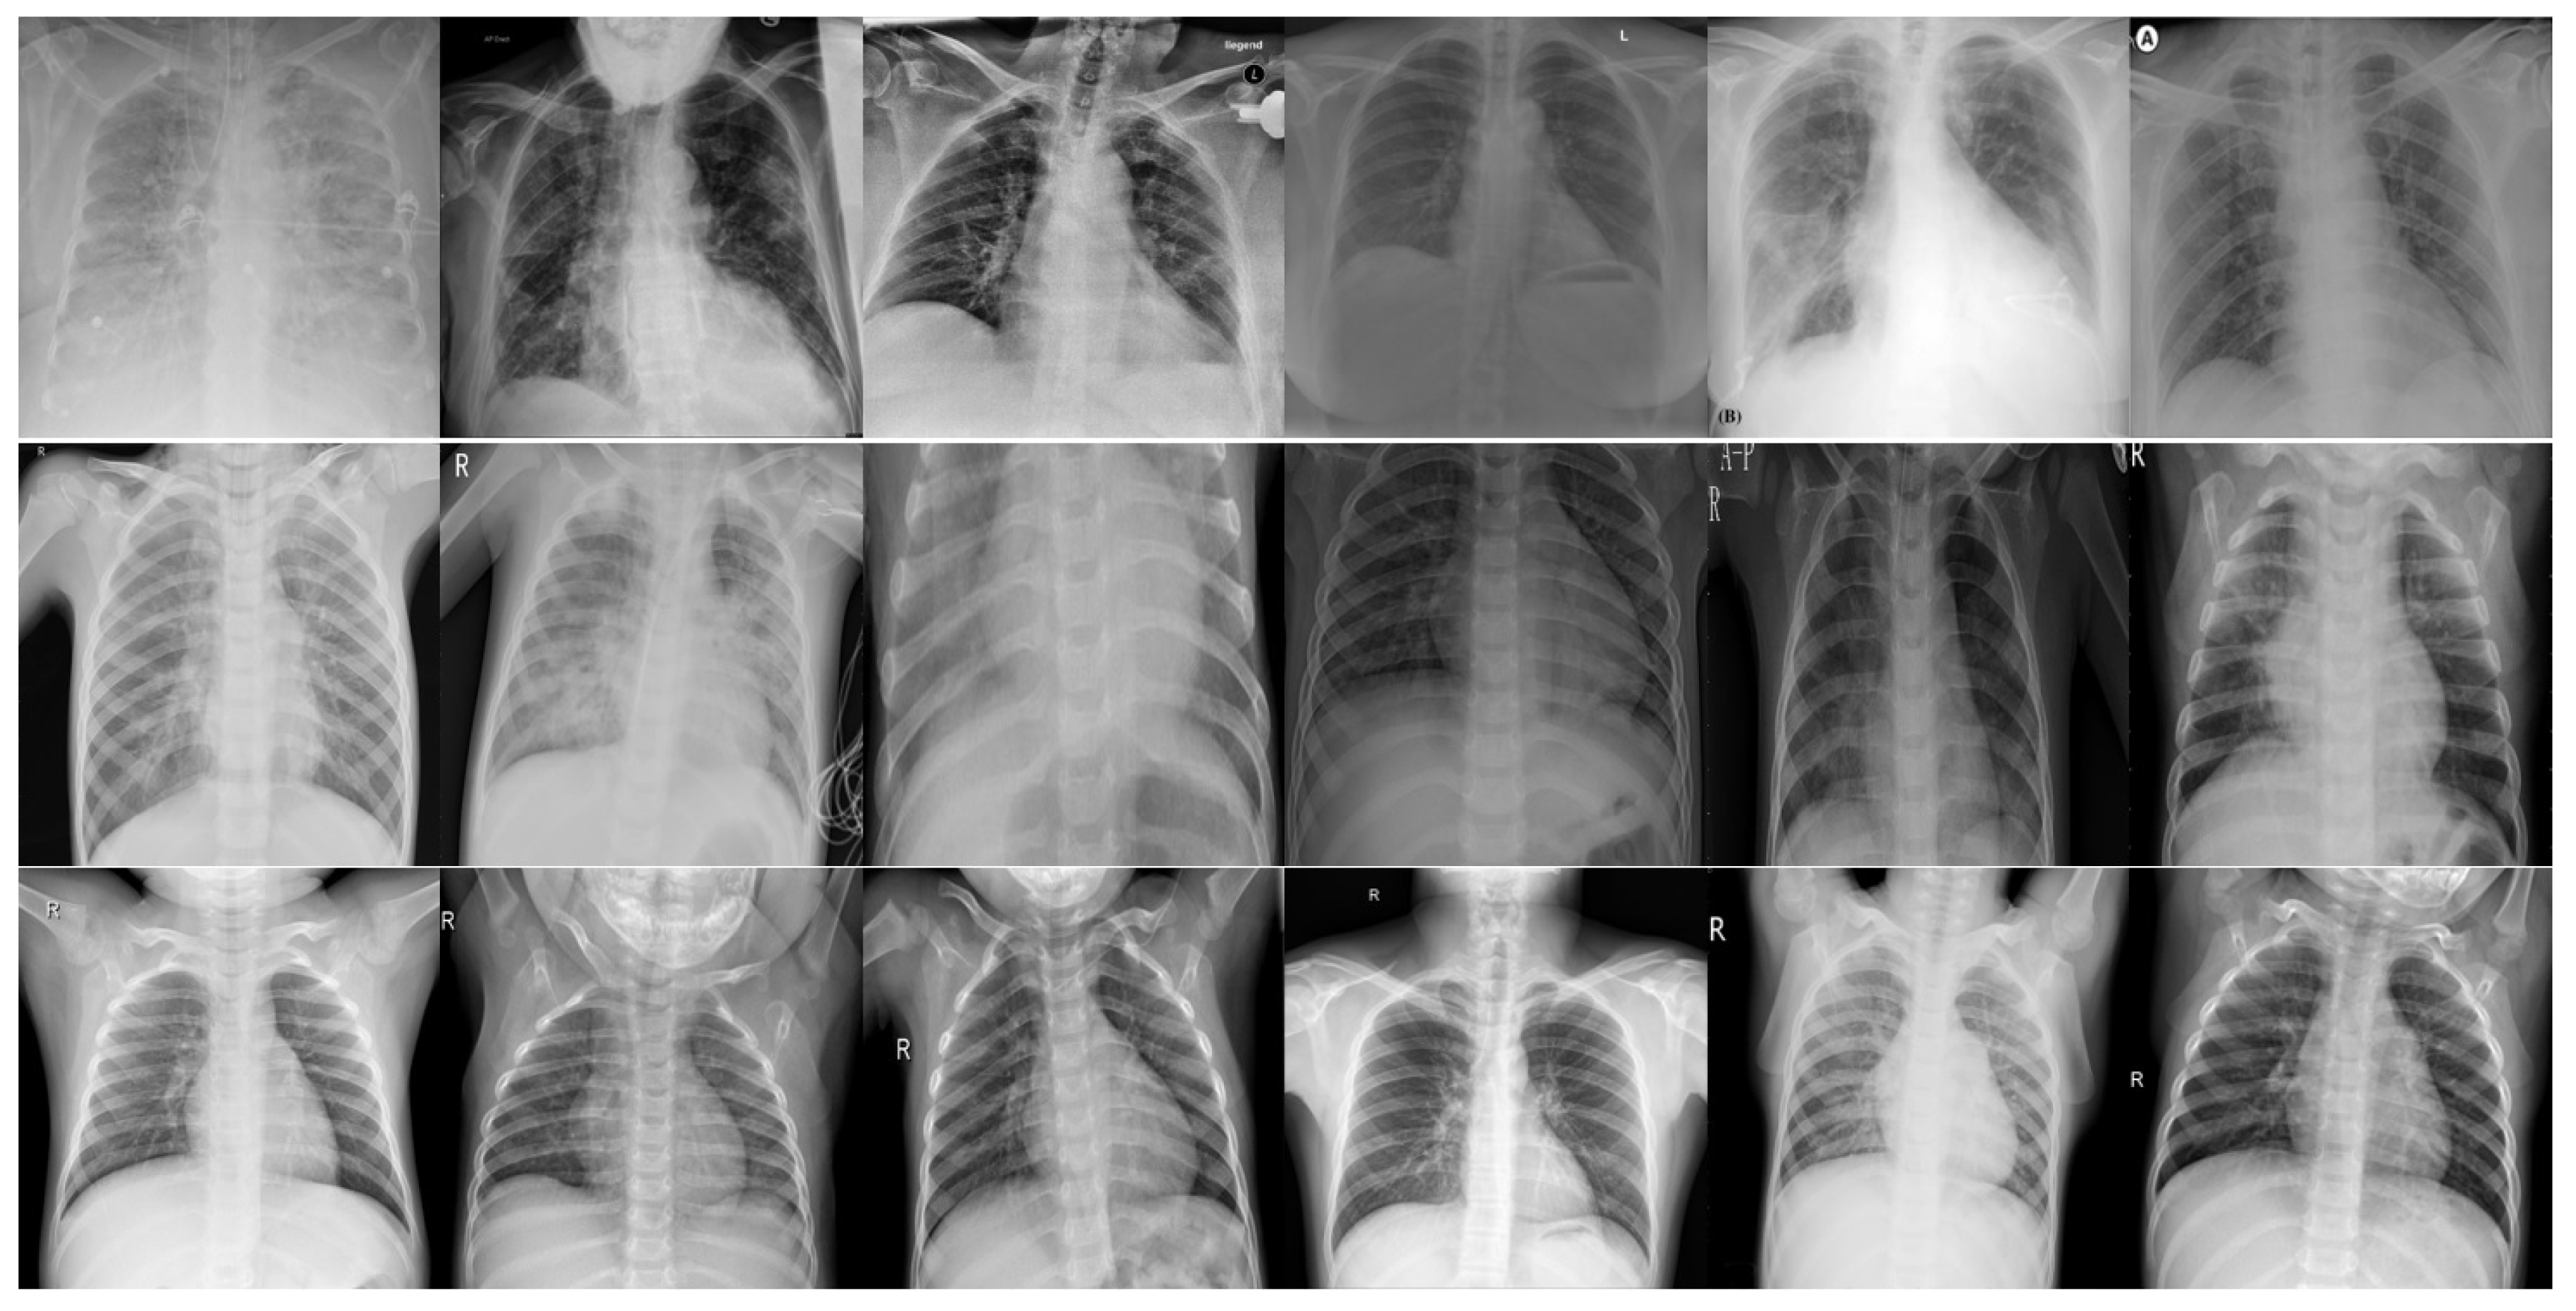

3.1. Chest X-ray Dataset

| Abdani et al. [2] | SPP-COVID-Net | • Applies spatial pyramid pooling module to extract features of various scales. | • The experiment has included X-ray images taken from a side view for COVID-19 cases, which will give advantage for that class detection performance. |